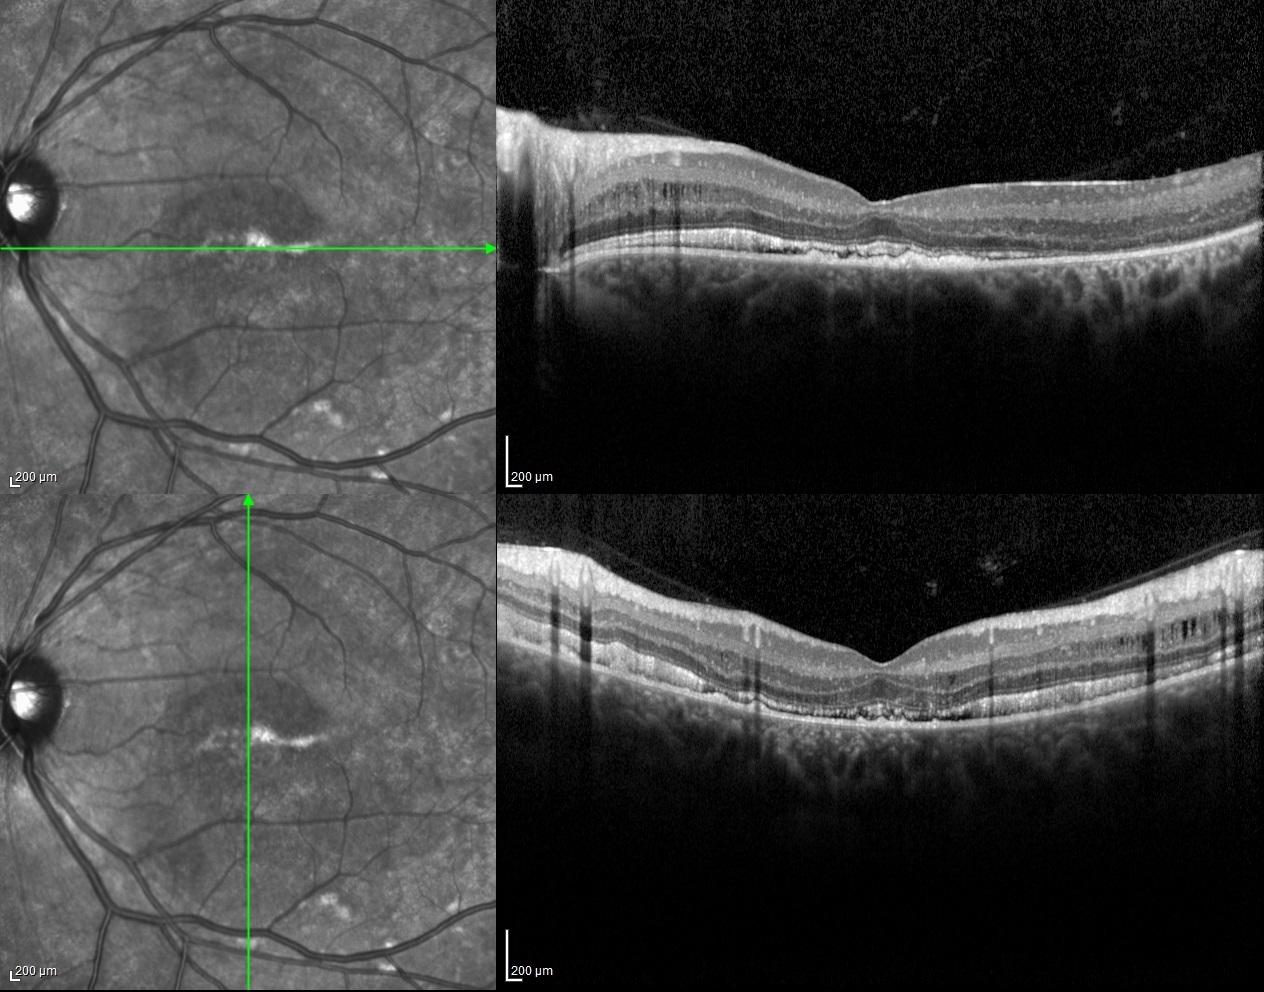

Spectral-domain optical coherence tomography of both eyes revealed minimally serous retinal detachment with dome shaped hyperreflective accumulation on RPE as well as retinoschisis in inner nuclear layers.